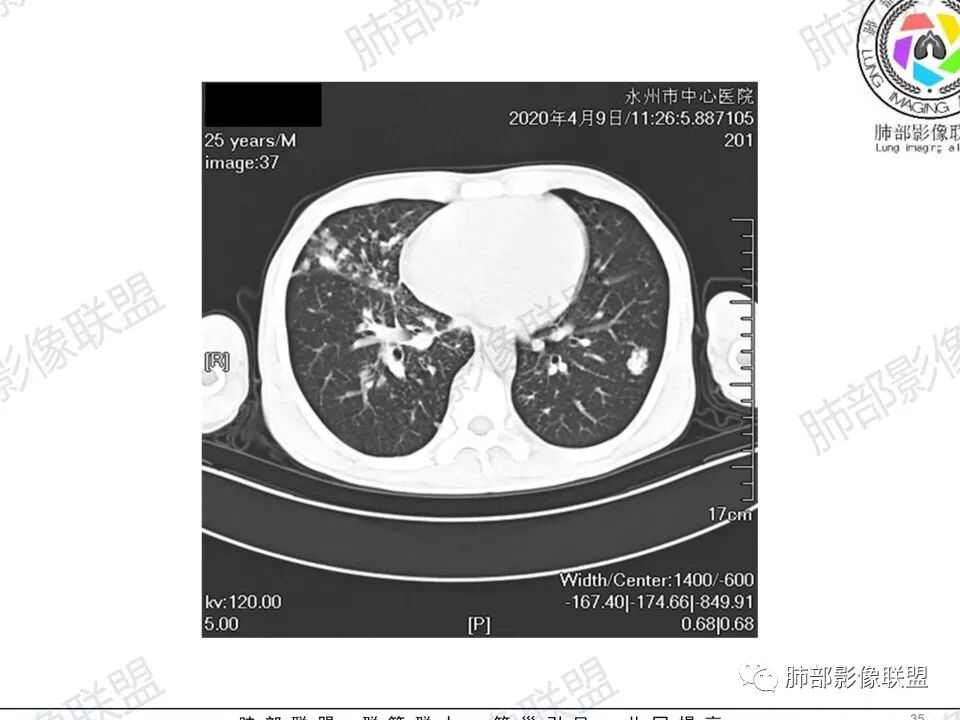

那个人:青年男性,慢性病程,咳嗽气促,伴盗汗胸痛。实验室,贫血,血沉快,C反应蛋白升高,低蛋白血症。影像,双肺散在斑片影,结节影,伴树芽,斑片影源支气管血管束分布,支气管走形自然,结节影有小空洞,有些周围有磨玻璃成分,小结节有些成串珠样改变,纵隔肺门淋巴结肿大,心腔低密度。考虑淋巴增值类疾病,结核?淋巴瘤?结节病?鉴别血管炎,实验室,影像不太支持

穿越七海的风:双肺多发结节斑片影,支气管通畅,间质浸润,纵隔肺门肿大淋巴结,考虑淋巴瘤?白血病浸润?结节病?

薏米:青年男性,慢性咳嗽,咳痰,气短,贫血,淋巴细胞低,尿隐血阴性,双肺散在多发结节,斑片,树芽影,支气管充气,肺门,纵隔淋巴结肿大,融合趋势,考虑淋巴瘤,鉴别结核

甄德强:年轻男性,慢性起病,双肺多发斑片影,结节影及粟粒点状影,纵隔及双肺门淋巴结肿大,似乎密度不均,结核中度症状,血沉快,一元论考虑结核,鉴别诊断结节病。

一切∮随缘:双肺多发大小不等结节,结节密度高,边缘清楚,部分结节内可见血管穿行,另右肺长条状实变影,内部可见支气管充气征,局部支气管壁增厚,双肺多发小树丫,双肺门及纵隔淋巴结肿大,部分融合,无增强,对淋巴结坏死无法判断,临床:年轻男性慢性病史急性加重,血象、CRP、ESR高,考虑一元论:结核(年龄加影像都符合),二元论:结节病或淋巴瘤+结核(建议CT增强及淋巴结穿刺),无原发肿瘤病史,癌性淋巴管炎代排。

刘L:纵隔多发淋巴结肿大,自肺门向上呈对称性分布,部分融合,内密度均匀;双肺散在分布大小不等结节,边界清晰,右肺中叶部分伴有实变,首先考虑结节病,建议增强扫描排除肺结核。

男性,25岁,咳嗽咳痰1年,气促两月,加重一天,伴盗汗胸痛。CT示双肺散在斑片影,结节影,树芽征,部分周围伴磨玻璃影,以右肺上叶明显,纵隔及双肺门可见多发淋巴结肿大,部分融合,青年人,病史较长,首先考虑结核,不排除结核合并结节病可能。

3、影像表现:双肺散在斑片影及结节影,部分结节内可见血管穿行,斑片影沿支气管血管束分布,近胸膜侧病变收缩不明显。部分中央淋巴间质增厚,小叶间隔增厚。病灶内支气管穿行,部分支气管略扩张。局部小结节呈串珠样改变。纵隔、肺门区、锁骨上及腋窝淋淋巴结肿大,部分有融合。心腔低密度。脾大。

2.双肺多发片影及结节影,边界可分辨,右肺中上叶较为密集,没有胸膜下分布优势。病灶实性密度为主,未见钙化及液化。

3.右肺较多微小结节,密度较为浅淡,部分沿血管束分布,未见沿小叶间隔及叶间裂分布结节影,未见典型的终末气道树芽。

4.病灶区域穿行支气管显示良好,未见壁增厚及管腔狭窄。

5.双肺门及纵隔淋巴结显著增大,这改变相当显眼。这里强调“双肺门”及“多发”!

增大的淋巴结密度偏低且均匀。此外患者有体表淋巴结增大。